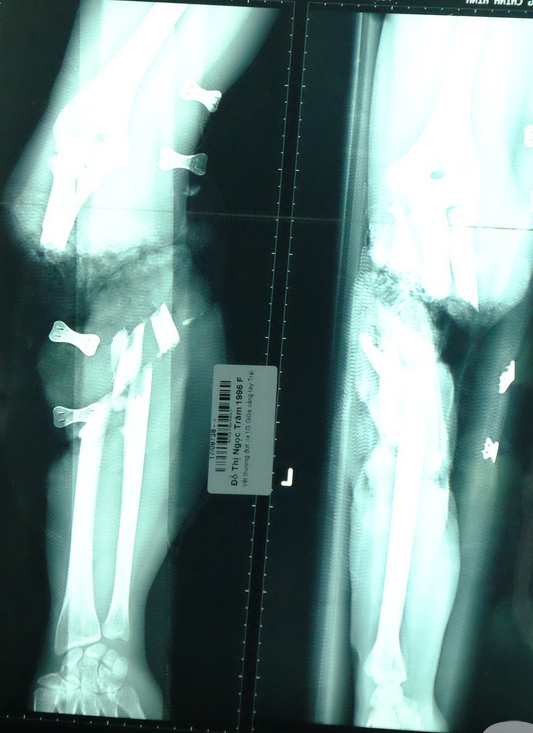

13/08/2017 01:52Theo mẹ đến nhà xưởng, bé trai 5 tuổi bị băng chuyền sản xuất cuốn đứt cánh tay

Trong lúc chơi đùa trong xưởng làm của mẹ, bé trai 5 tuổi đánh rơi dép gần khu vực băng chuyền sản xuất. Cố với lấy chiếc dép, cánh tay em không may bị băng chuyền sản xuất cuốn, tình trạng vô cùng nguy kịch.

Theo lời kể từ người nhà, sáng 10-8, bé P. (5 tuổi, ngụ Kiên Giang) theo mẹ đến xưởng làm. Trong lúc chơi đùa, em đánh rơi chiếc dép gần băng chuyền sản xuất. Trong lúc cố rướn người lấy chiếc dép tay của bé bị vướng vào băng chuyền sản xuất. Hậu quả là cánh tay phải của bé trai bị cuốn đứt lìa. Sau khi được một BV ở Kiên Giang phẫu thuật nối 1/3 cánh tay rời ra, bé được chuyển tiếp đến BV Chấn thương Chỉnh hình TP HCM vì vết thương không phục hồi tốt.

|  			 Ảnh siêu âm cho thấy 1/3 cánh tay bé trai bị đứt rời.  |

BS Võ Hòa Khánh, BV Chấn thương Chỉnh hình TP HCM cho biết, khi nhập viện, cánh tay phải bệnh nhi đã trong tình trạng sưng đau, đầu chi nhạt, mạch quay khó bắt, các ngón tay không cử động được. Vì tình trạng quá nặng, các bác sĩ buộc phải đoạn chi 1/3 cánh tay phải để giữ tính mạng cho đứa bé.

Theo BS Khánh, từ lúc bệnh nhi gặp nạn đến khi được chuyển đến BV Chấn thương Chỉnh hình TP.HCM là 20 giờ. Vì đã qua thời gian vàng nên cánh tay của bệnh nhi không thể cứu vãn.

Bác sĩ Khánh khuyến cáo người dân khi gặp nạn đứt rời chi cần sơ cứu đúng cách và nhanh chóng đưa đến cơ sở y tế gần nhất. Lưu ý cho phần đứt rời vào túi nilon, buộc kín lại và bảo quản trong đá lạnh nhưng không cho tiếp xúc trực tiếp vì dễ làm mạch máu và dây thần kinh bị hỏng.